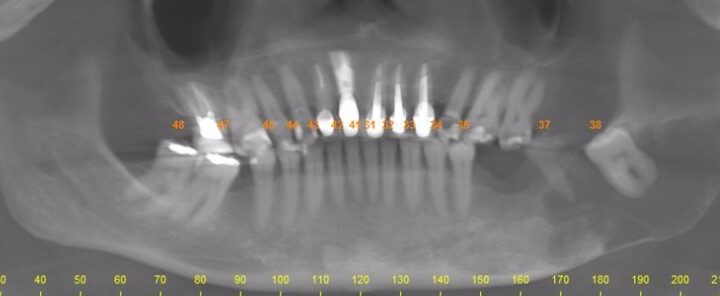

A patologia bucal e maxilofacial é uma especialidade da odontologia que se interessa pelo estudo do diagnóstico e tratamento das lesões da boca e face. O Cirurgião bucomaxilofacial é o responsável pelo diagnóstico das lesões e tratamento das patologias benignas. Os tumores malignos são tratados por cirurgião de cabeça e pescoço.

Na presença de qualquer alteração na boca ou rosto, que permaneça por mais de 15 dias, o cirurgião dentista deve ser procurado e, caso necessário, encaminhar para o cirurgião bucomaxilofacial.